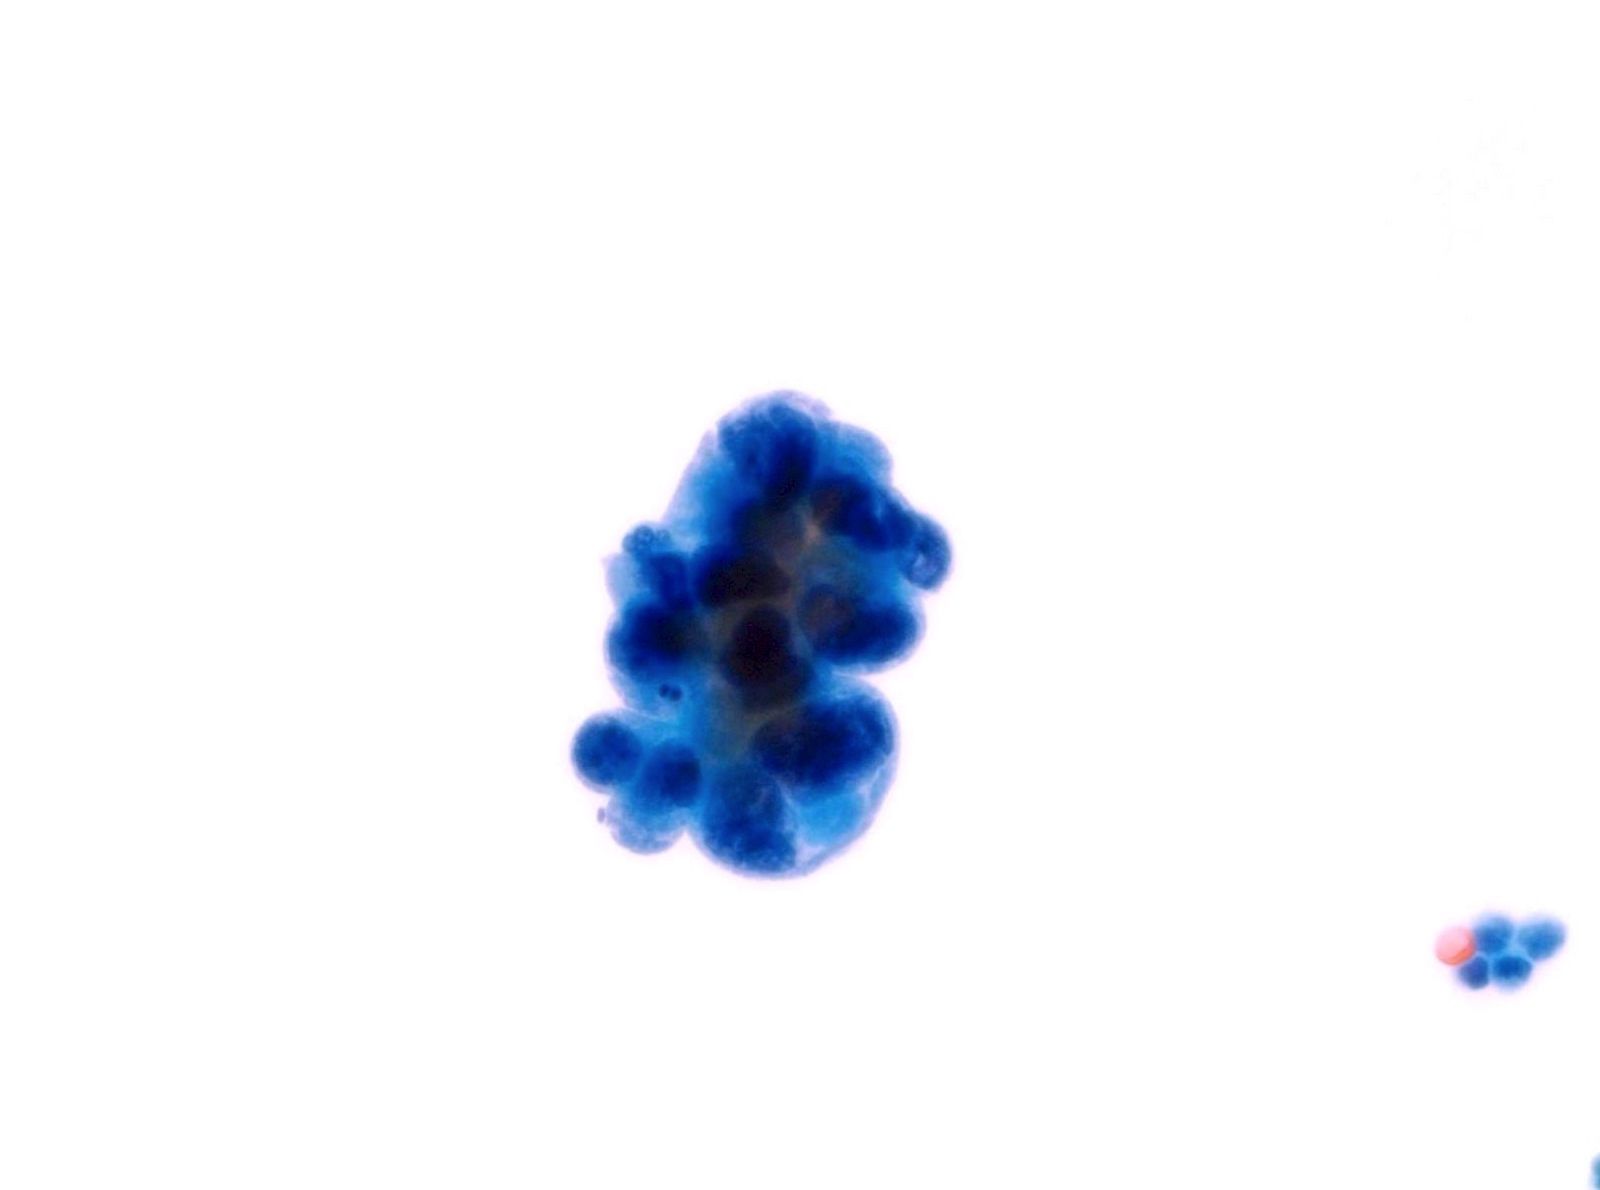

Low Grade Urothelial Neoplasia (LGUN)

- LGUN is a combined cytologic term for low grade papillary urothelial neoplasms, which includes urothelial papilloma, papillary urothelial neoplasm of uncertain malignant potential (PUNLMP) and low grade papillary urothelial carcinoma (LGPUC)

- Definitive diagnosis of LGUN is possible only in the presence of this cytologic criteria (regardless of voided urine or instrumented urine):

- 3 dimensional cellular papillary clusters with fibrovascular cores including capillaries

- Cellular papillary clusters are defined as clusters of cells with nuclear overlapping forming papillae

- The following cytologic features should be categorized as NHGUC:

- 3 dimensional cellular clusters without fibrovascular cores

- Increased numbers of single monotonous (non umbrella) cells

- Cytoplasmic homogeneity

- Nuclear border irregularity

- Increased N/C ratio

- A comment may be added to suggest LGUN in these cases without definitive cytomorphologic features

- Rate of progression is 0% for papillomas, 3.6% for PUNLMP and 5 - 25% for LGPUC (WHO / ISUP classification (2004))